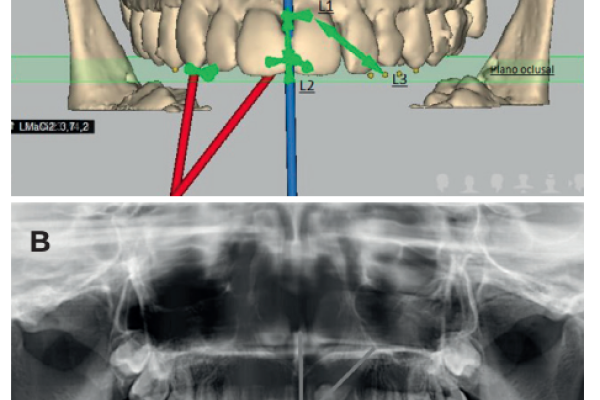

Radiographic diagnosis of impacted maxillary canines: Comparison between two and three dimensions